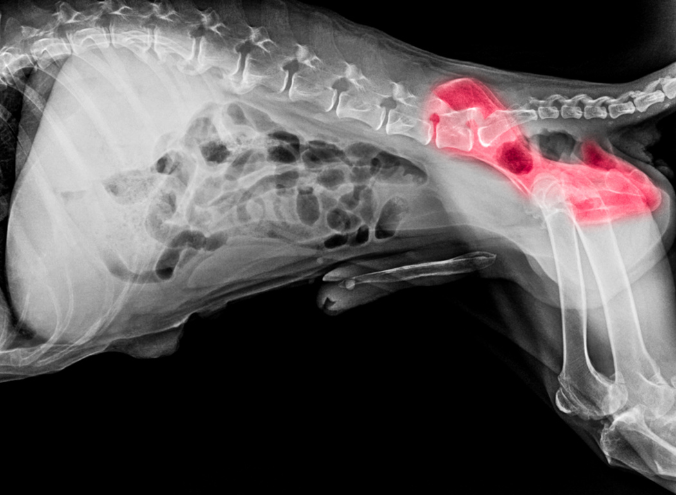

La displasia de cadera en perros es una condición ortopédica que afecta la articulación coxofemoral. Se presenta cuando la cabeza del fémur y la cavidad de la cadera no tienen una congruencia adecuada, lo que genera inestabilidad articular.

Esta alteración produce un movimiento anormal que, con el tiempo, puede provocar inflamación, desgaste del cartílago y cambios degenerativos en la articulación. Su origen es multifactorial e involucra predisposición genética, crecimiento, alimentación y nivel de actividad.

El diagnóstico se complementa con estudios de imagen. Las radiografías permiten valorar la congruencia de la articulación, identificar subluxaciones y observar cambios degenerativos. De acuerdo con la American College of Veterinary Surgeons, estos estudios son fundamentales para confirmar la displasia de cadera en perros y determinar su grado de afectación.